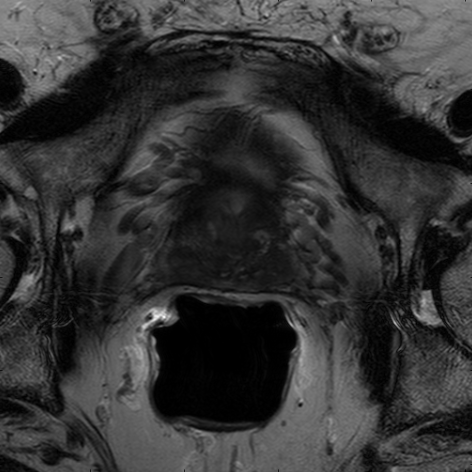

We trained our network on 77 patients. The input images and the manual ground truth annotation are shown in Fig.4. As we have described above, these images were acquired from different patients, and these images include the clinical variability. To evaluate our method, we randomly selected 4 patients with 64 images before training. These images do not take part in training and the prostate has been manually pre-delineated by a radiologist, which were used as the ground truth to evaluate the performance of automatic segmentation. We also selected dice coefficient as the evaluation method[30]. And to validate our method against U-Net and fully convolutional networks (FCNs), we used the same dataset to train and test the U-Net and FCNs.

To intuitively compare the proposed method with U-Net and FCN, the segmentation results of some representative and challenging samples are shown in Fig 5. It can be seen that these prostate images have fuzzy boundaries and the pixel intensity distributions are inhomogeneous both inside and outside of the prostate. Besides, both prostate and nonprostate regions have similar contrast and intensity distributions. All of these phenomenons make the segmentation difficult.